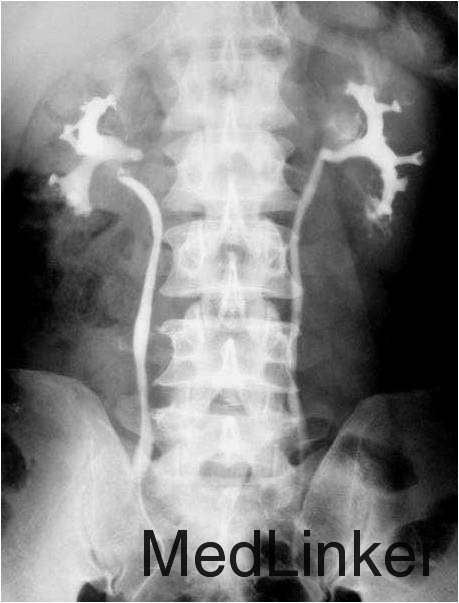

查体:右肾区轻度叩击痛,右侧输尿管深压痛,彩超检查右肾泥沙样结石。予以行逆行插管造影检查,发现右侧输尿管扭曲。膀胱,尿道未见异常